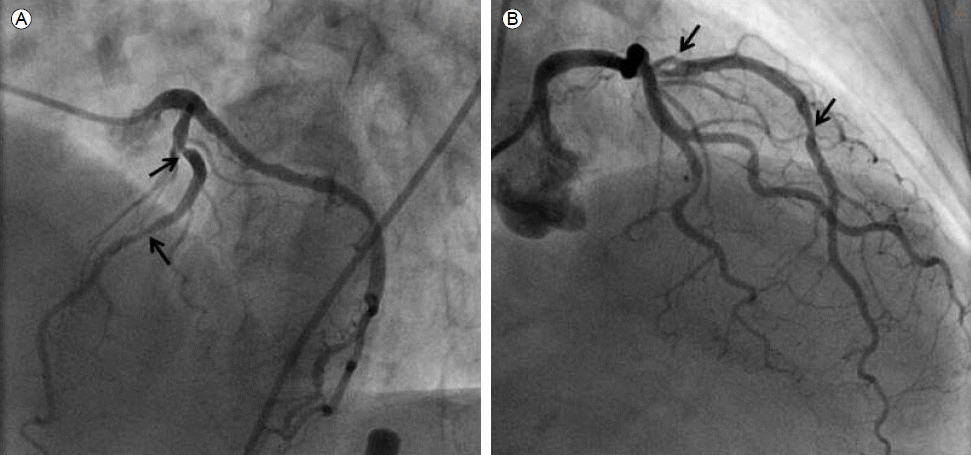

Figure 3.

(A) A final angiogram, right anterior oblique cranial view. (B) Longitudinal IVUS images of the proximal LAD after additional stent implantation. B-1: Previously shown stent-in-stent appearance B-2: Previously shown stent fracture; B-3: Previously shown incomplete stent apposition.

74세 여자가 1개월 전부터 발생한 흉통을 주소로 본원에 내원하였다. 환자는 제2형 당뇨병을 진단받고 투약 중이었으며 그밖에 특이 병력, 과거력 및 가족력은 없었다. 심전도와 심초음파에서는 이상소견이 없었으나 심근 관류 단일 광자 방출 전산화 단층 촬영(single photon emission computed tomography, SPECT)에서는 좌전하행지 영역에 가역적인 병변이 있음을 확인하였다. 이후 시행한 관상동맥 조영술에서 좌전하행지의 근위부와 중간부에서 심한 협착 소견을 확인할 수 있었다(Fig. 1). 일차적으로 풍선 확장술을 시행하였고 3.5 × 15 mm, 2.75 × 14 mm zotarolimus 방출 스텐트(Endeavor resolute, Medtronic, Minneapolis, USA)를 좌전하행지의 근위부와 중간부에 각각, 중복(overlapping) 없이 12기압으로 확장하여 삽입하였다. 이후 관상동맥 조영술에서 최적의 결과를 얻었으며(Fig. 2A) 삽입된 스텐트를 평가하기 위해 혈관 내 초음파(intravascular ultrasound, IVUS)를 시행하였다. 혈관 내 초음파 카테터(Atlantis SR Pro, Boston Scientific Corporation, Boston, USA)를 좌전하행지의 원위부에 위치시킨 후 자동 후퇴를 하면서 영상을 얻었다. 그 결과 스텐트는 관상동맥 내에 적절하게 삽입되어 있었고, 불완전 확장(underexpansion) 소견은 관찰되지 않았다(Fig. 2B, 2B-1~2B-3). 이후 혈관 내 초음파를 수동으로 당겨내던 중 카테터의 끝부분(tip of IVUS)이 근위부의 스텐트 위치에 다다랐을 때 저항이 느껴졌다. 저자들은 일단 가이딩 카테터 및 유도철선, 초음파 카테터를 한꺼번에 조심스럽게 당겼으나 결국 초음파 카테터는 제거할 수 없었다. 그래서 일단 혈관내 초음파 카테터의 유연성을 높이기 위해 탐촉자(transducer)와 그것을 둘러싸고 있는 집(sheath)을 분리하고 탐촉자를 먼저 제거한 뒤 카테터 집을 당겼다. 이후 제거된 카테터 집의 끝(sheath tip of guidewire exit port)이 찢어진 걸 확인할 수 있었으며(Fig. 2C) 직후 시행한 조영술에서 근위부 스텐트 부분에 이전 조영에서는 보이지 않던 흐릿한 영상(haziness)을 관찰할 수 있었다(Fig. 2D). 이를 면밀히 관찰하고자 새로운 가이딩 카테터, 유도철선을 적절히 위치시킨 뒤 혈관 내 초음파를 시행하였으며 스텐트 내 스텐트 현상(stent in stent appearance; 스텐트의 완전 골절 이후 골절된 스텐트의 원위부가 근위부로 중첩되어 들어가는 현상, Fig. 2E-1), 스텐트 골절(stent fracture, Fig. 2E-2) 그리고 불완전 스텐트 부착(incomplete stent apposition, Fig. 2E-3)의 발생을 확인할 수 있었다. 이를 해결하기 위해 3.5 mm 크기의 풍선을 이용해 혈관 확장술을 시행한 뒤 4.0 × 24 mm zotarolimus 방출 스텐트(Endeavor resolute, Medtronic, Minneapolis, USA)를 이전 삽입한 근위부 스텐트에 중복하여 좌주간지 입구까지 삽입하였다. 이후 확인한 혈관 내 초음파에서는 스텐트가 혈관벽에 잘 부착되어 있음을 확인할 수 있었으며 조영술에서도 스텐트 변형은 더 이상 관찰할 수 없었다(Fig. 3). 환자는 다른 합병증 없이 퇴원하였으며 9개월 후 추적 관상동맥 조영술 및 혈관 내 초음파에서 스텐트가 잘 보존되어 있음을 확인할 수 있었다.